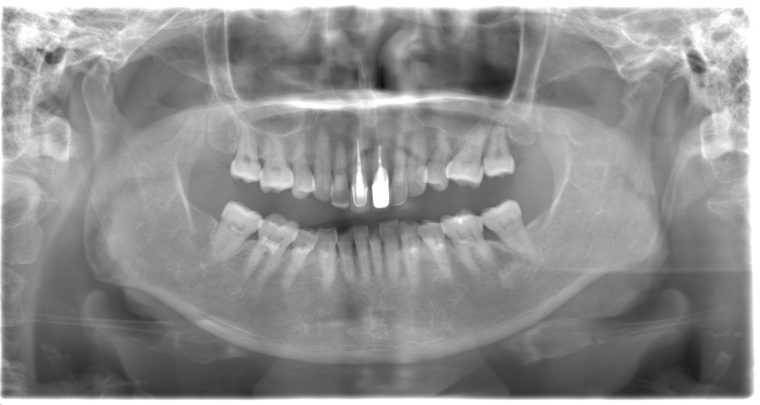

レントゲン写真

症例

年齢・性別 75歳・女性

主訴 主訴:左上奥の歯ぐきが腫れた

治療部位:左上下奥歯、右下奥歯

治療内容 1.歯周ポケット検査、歯磨き指導、抗生物質塗布

2.縁上の歯石除去

3.縁下の歯石除去

4.再評価

5.定期検診(3ヶ月おき)

特記事項 ・65年前に矯正治療をしてから歯をずっと大切にしてきたので、なるべく抜歯はしたくない。

・上の前歯は10年前にお孫さんがぶつかってきて、神経の治療をした。

担当者所見 左上は歯ぐきがかなり腫れていたが、歯石除去とホームケア(歯ブラシ、歯間ブラシSサイズ、ミクリンタフトブラシ)と抗生物質(軟膏)により腫れが落ち着いた。

そして現在は定期検診で毎回異常がないか確認し、ホームケアではなかなか届かない歯周ポケット内のクリーニングを行っています。一度骨が溶けてしまっている為、歯周ポケットは残りますが、その後再発することは今のところなく、定期検診で今後もしっかり管理していきます。